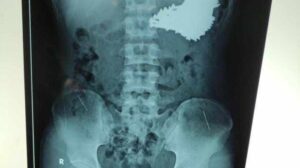

Cicin Listia Vitasari, meninggal akibat puluhan benda logam di perutnya

Bulan Agustus 2009, Cicin mengaku sakit perut hingga lemas dan sulit bernafas. Oleh orang tuanya, ia dibawa ke RSUD Situbondo dan setelah dilakukan rontgen ditemukan beberapa benda logam di perut seperti silet, tusuk konde, biji streples, kawat dan jepit rambut. Kondisi Cicin melemah karena infeksi saluran kencing, sehingga RSUD Situbondo tidak berani melakukan operasi. Tidak tahan dengan sakitnya, Cicin pun menghembuskan nafas terakhirnya pada Sabtu 29 Agustus 2009 dini hari sebelum dirujuk ke RSU dr Soetomo Surabaya.